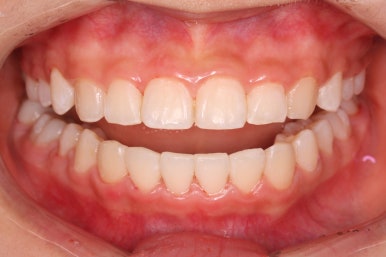

치료 종료 후의 모습입니다.

치아들이 가지런하게 되었고, 나오지 못하던 치아도 잘 나와서 가지런해졌습니다.

해당 부위 앞뒤로 쓰러져 있던 치아들도 축이 바로 잡혔고, 자연스레 위-아래 치아의 중앙선도 맞아졌습니다.

얼굴 모습의 큰 변화 없이 양호한 모습 그대로 마무리가 되었고, 웃을 대 위아래 치아의 중앙이 안맞았던 부분도 개선되었습니다.

치아가 잘 올라온 것을 볼 수 있습니다.